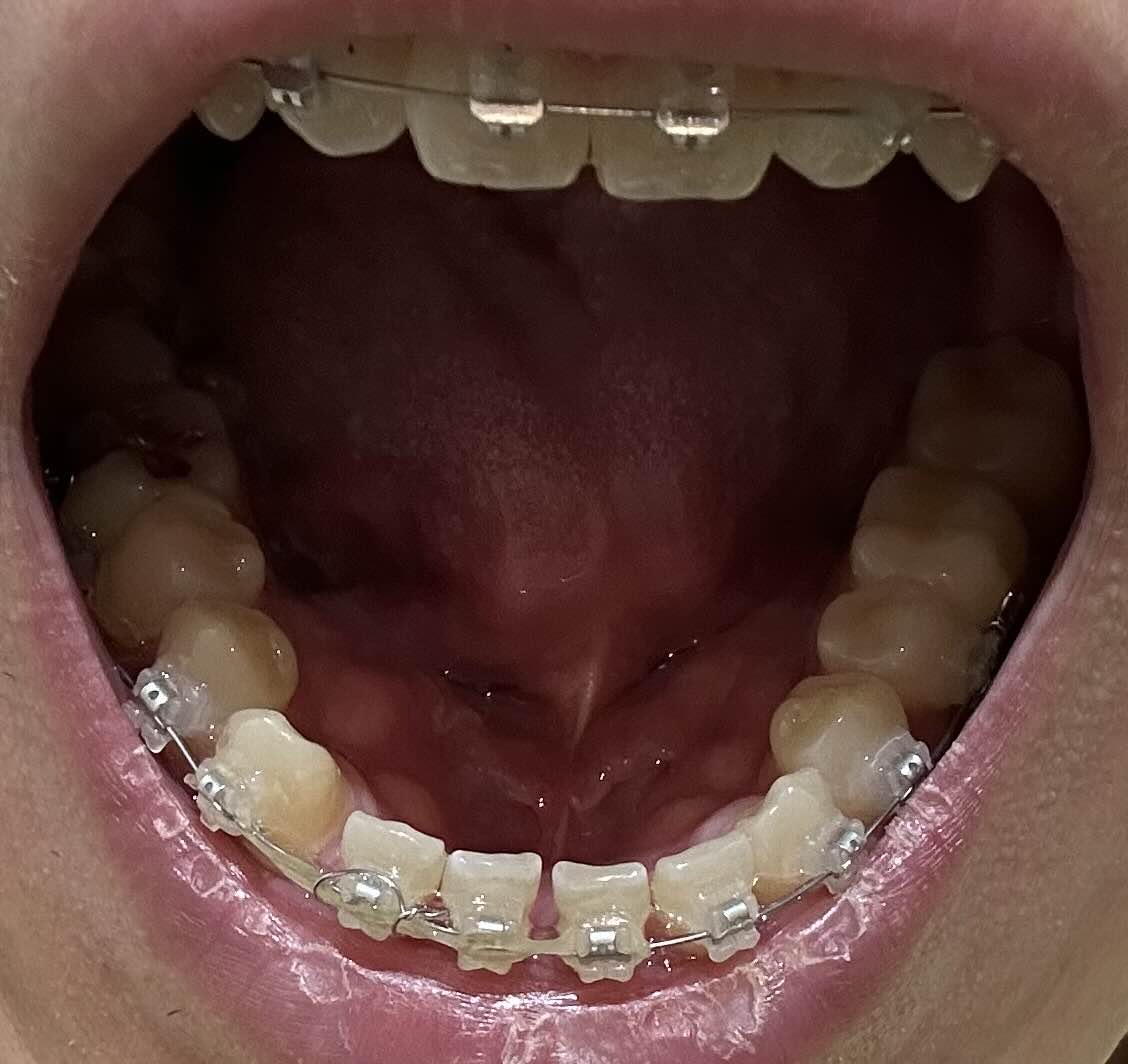

우선 교정을 시작하기 전의 모습이에요. 앞니가 많이 벌어진 상태로 점점 조금씩 돌아가고 있는 모습이 정말 보기 싫었는데요. 사실 거울을 보면서도 크게 못 느꼈던게 사실이었기 때문에 아무 생각을 안하고 있었는데, 확실히 교정을 하고 나서 모습을 보니까 잘 한거 같아요.

9월 이전 교정 전 모습

확실히 교정기를 장착하기 전에 많이 벌어진 모습이 보여요. 특히 앞니는 조금씩 더 돌아가고 있어서 교정을 고민하던 중에 결정하게 된 이유기도 해요.